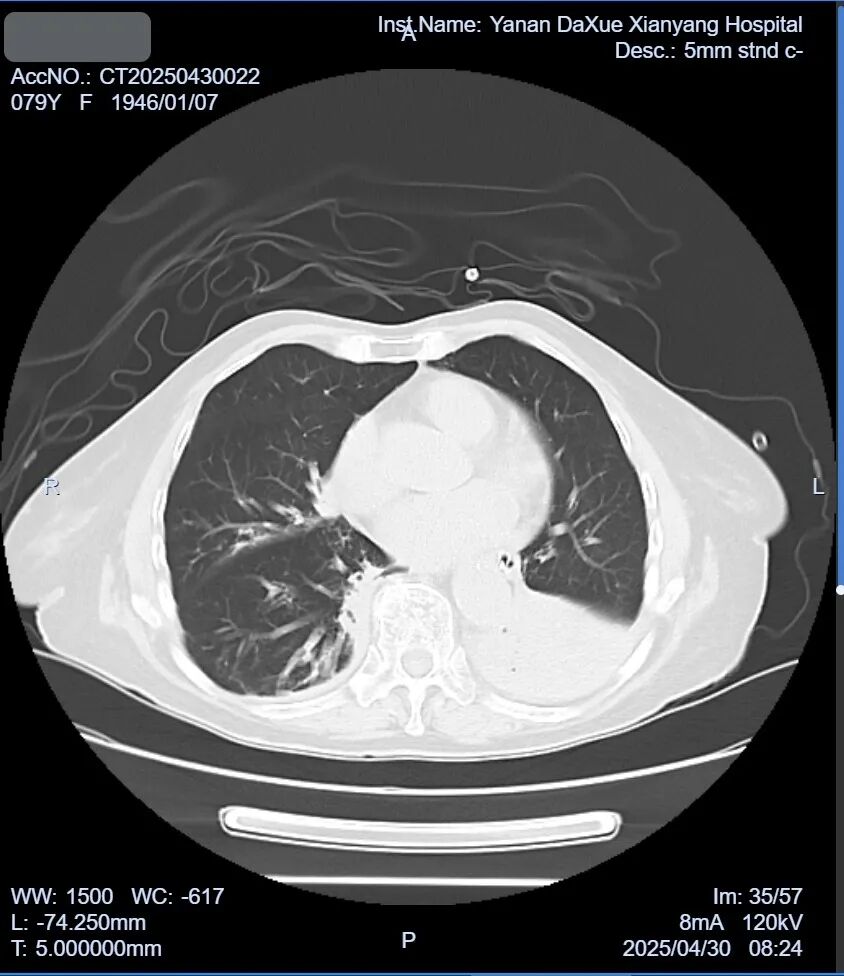

入院后胸部CT檢查明顯的肺部墜積性肺炎(圖2),淋巴細胞亞群異常,B淋巴細胞亞群比例27.6%(圖3)。

圖2.入院時胸部CT